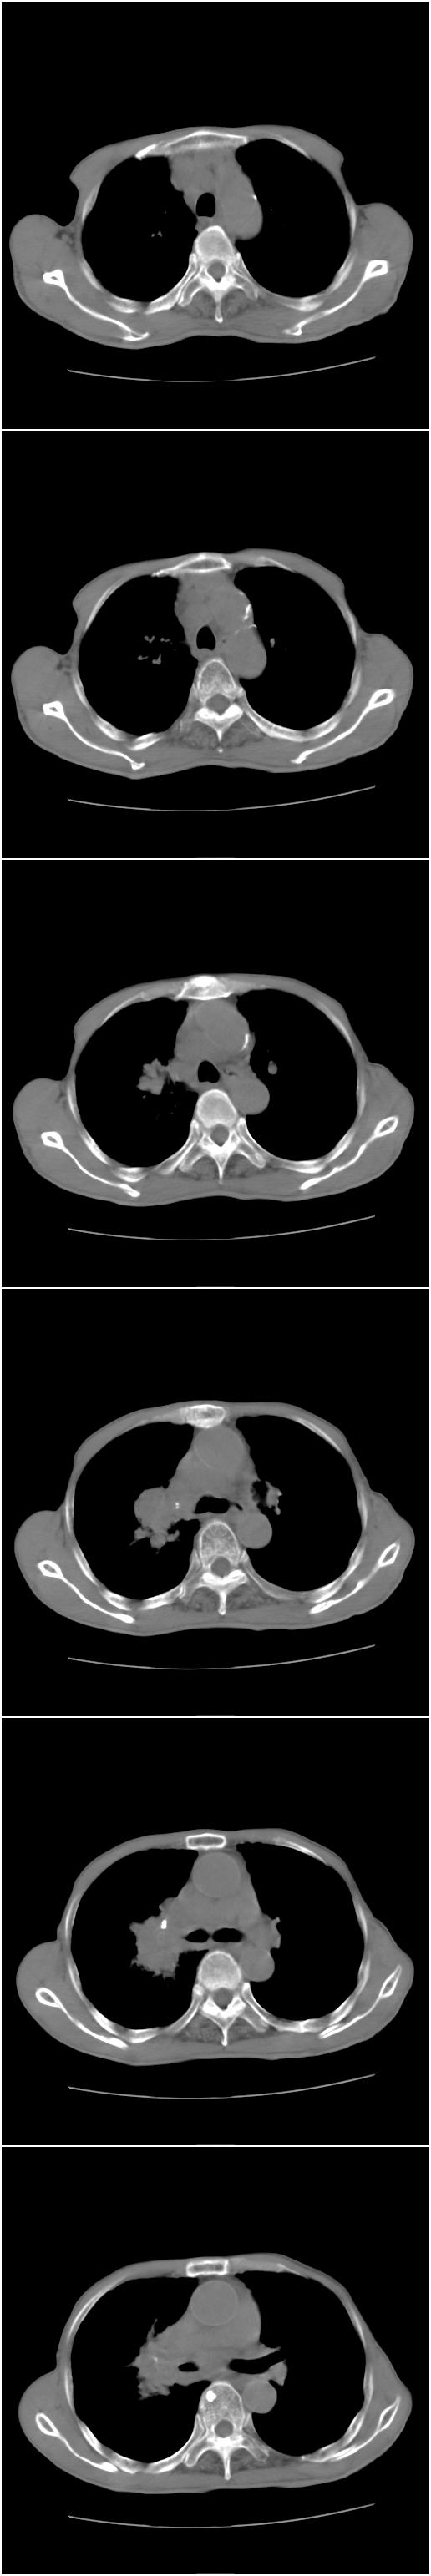

标题: CT12024:男,77岁。咳嗽两月余,气喘一月,13年前岑作贲门 [打印本页]

标题: CT12024:男,77岁。咳嗽两月余,气喘一月,13年前岑作贲门

1、右侧中心型肺癌,右肺门,纵隔淋巴结转移可能性大。

2、贲门癌术后所见。

右侧中央型肺癌伴右肺门及纵隔淋巴结转移.

1 右肺中心型肺癌伴右肺门及纵隔淋巴结转移.

2  左肺贲门癌术后改变.